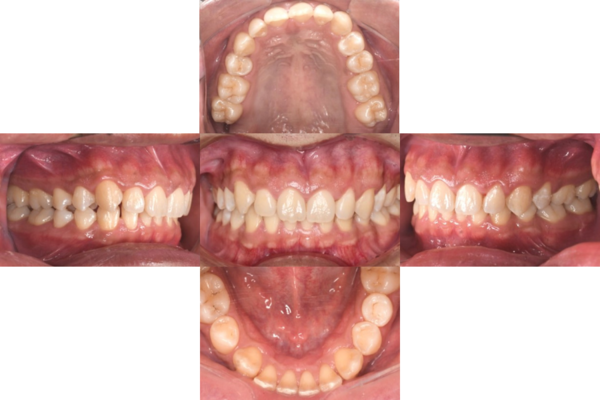

症例3

来院2回目、TBI後

症例

SRP後

初診時、TBI前

基本情報

年齢・性別 27歳・男性

主訴 主訴:左右下の歯ぐきに違和感がある

治療部位:全顎

治療内容 1.歯周基本検査、レントゲン撮影、口腔内写真、歯磨き指導、歯石除去、着色除去

2.SRP(スケーリングルートプレーニング)、再評価

その他

3.親知らずの抜歯

4.カリエス処置:右上1.2.3左上1.2.3右下6左下7CR(レジン充填)、右下7セラミックIn

5.定期検診

治療期間 6ヶ月

治療費 ※歯周基本治療の費用:PMTC以外保険診療3割負担

合計:19,680円

1.初診検査(歯周ポケット検査.レントゲン撮影):3,010円

2.歯磨き指導、歯面の歯石除去:1,410円

3.PMTC(自由診療):5,500円

4.SRP(歯周ポケット内の歯石除去)×4回:約2,000円/回

5.再評価:1,760円

(2023年12月現在)

リスク・副作用 ・最初は歯磨きをすると歯ぐきから出血するが毎日ホームケアを続けることで出血が徐々になくなる

・歯ぐきが腫れている状態が改善されると歯ぐきが引き締まり退縮するため、歯ぐきが下がったように感じることがある

・歯ぐきが引き締まると歯間が開いたように感じることがある

・歯ぐきが引き締まると知覚過敏の症状がでる可能性がある

・一度歯石を除去しても毎日のホームケアを怠ると再度歯石がつく

・治療後も再発を防ぐために定期的なメインテナンスが必要である

治療方針 1.初診検査(レントゲン撮影、口腔内写真、歯周検査、歯磨き指導)

2.歯磨きチェック、歯石除去、PMTC

3.SRP

4.再評価

特記事項 ・歯科医院は今回初めて

・タバコは24歳まで3年ほど吸っていたが健康のためにやめた

・親知らずは右下以外抜歯

・歯ブラシはルシェロP20M、補助用具はフロスを処方

担当者所見 全体的に歯と歯ぐきの境目に歯垢(細菌の塊)が残り、日々のホームケアで落とし切れていなかったことと、歯科医院への定期検診の習慣がなかったことから、全顎的な歯肉炎になってしまったと考えられる。

歯周基本治療とホームケアで歯ぐきの腫れや歯周ポケット、出血率などかなり改善されたが、出血がまだ0%ではない為、引き続き歯ブラシの当て方をお伝えしつつ今後は定期検診で3ヶ月おきに再発しないよう一緒に管理していく。